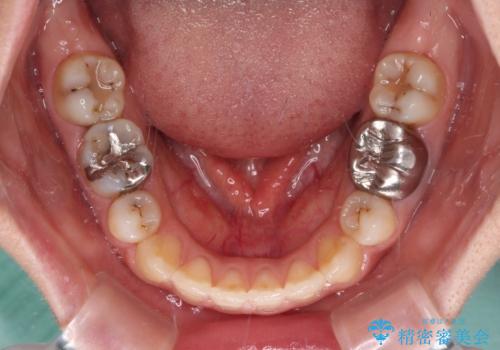

治療は順調に進み、予定された期間で終了することができました。

装置除去後には、スッキリとした口元となり、大変満足していただきました。